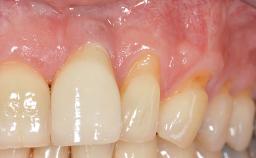

Implant Placement in the Esthetic Zone and Coverage of Multiple Gingival Recessions

This case illustrates use of a modified ‘tunnel’ technique, which has been shown to be highly effective in root coverage procedures. The tunnel technique is used to achieve soft-tissue augmentation across the anterior area, including the planned implant site, using collagen matrix as grafting material. The patient is a 47-year-old woman with high esthetic expectations. Her main concern was the appearance of the anterior teeth and their “elongation”.